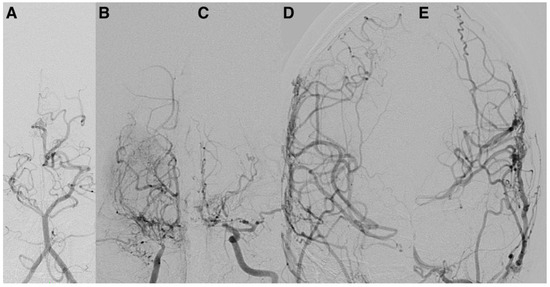

Representative postoperative angiographic images are shown in Figure 1, Figure 2 and Figure 3. The mean operative time was 3.2 h and the average length of hospital stay was 7 days. All patients were monitored in the pediatric intensive care unit for 24–48 h before being transferred to the ward.

Figure 1. Postoperative digital subtraction angiography (DSA) of the right internal carotid artery (ICA) in anteroposterior (A) and lateral (B) views demonstrate severe stenosis of the terminal ICA and a thread-like appearance of the M1 and A1 segments. There is reconstitution of the middle cerebral artery (MCA) and anterior cerebral artery (ACA) via lenticulostriate collaterals, consistent with Suzuki stage III. The parenchymal phase (C,D) reveals a focal hypovascular zone, which is indicative of decreased capillary density and chronic ischemic changes secondary to Moyamoya disease. DSA: digital subtraction angiography; ICA: internal carotid artery; MCA: middle cerebral artery; ACA: anterior cerebral artery.